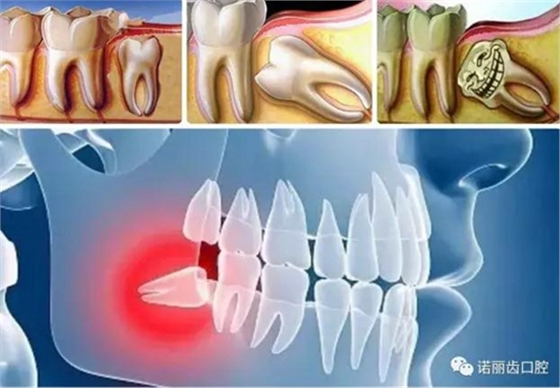

那么,如何判斷自己的智齒生長情況呢?除了有明顯的疼痛感你需要做相應的處理,同時通過X線可以觀察智齒的數(shù)量和位置以及具體情況。

經(jīng)過拍片探查,確定了以下情況的,那么,果斷的,禍患不可留?。?/p>

阻生智齒

這是比較常見的一種問題,該種智齒通常埋在齒槽骨的里面,如果經(jīng)常發(fā)生炎癥,或是診斷會有病灶發(fā)生的時候,就必須拔除。